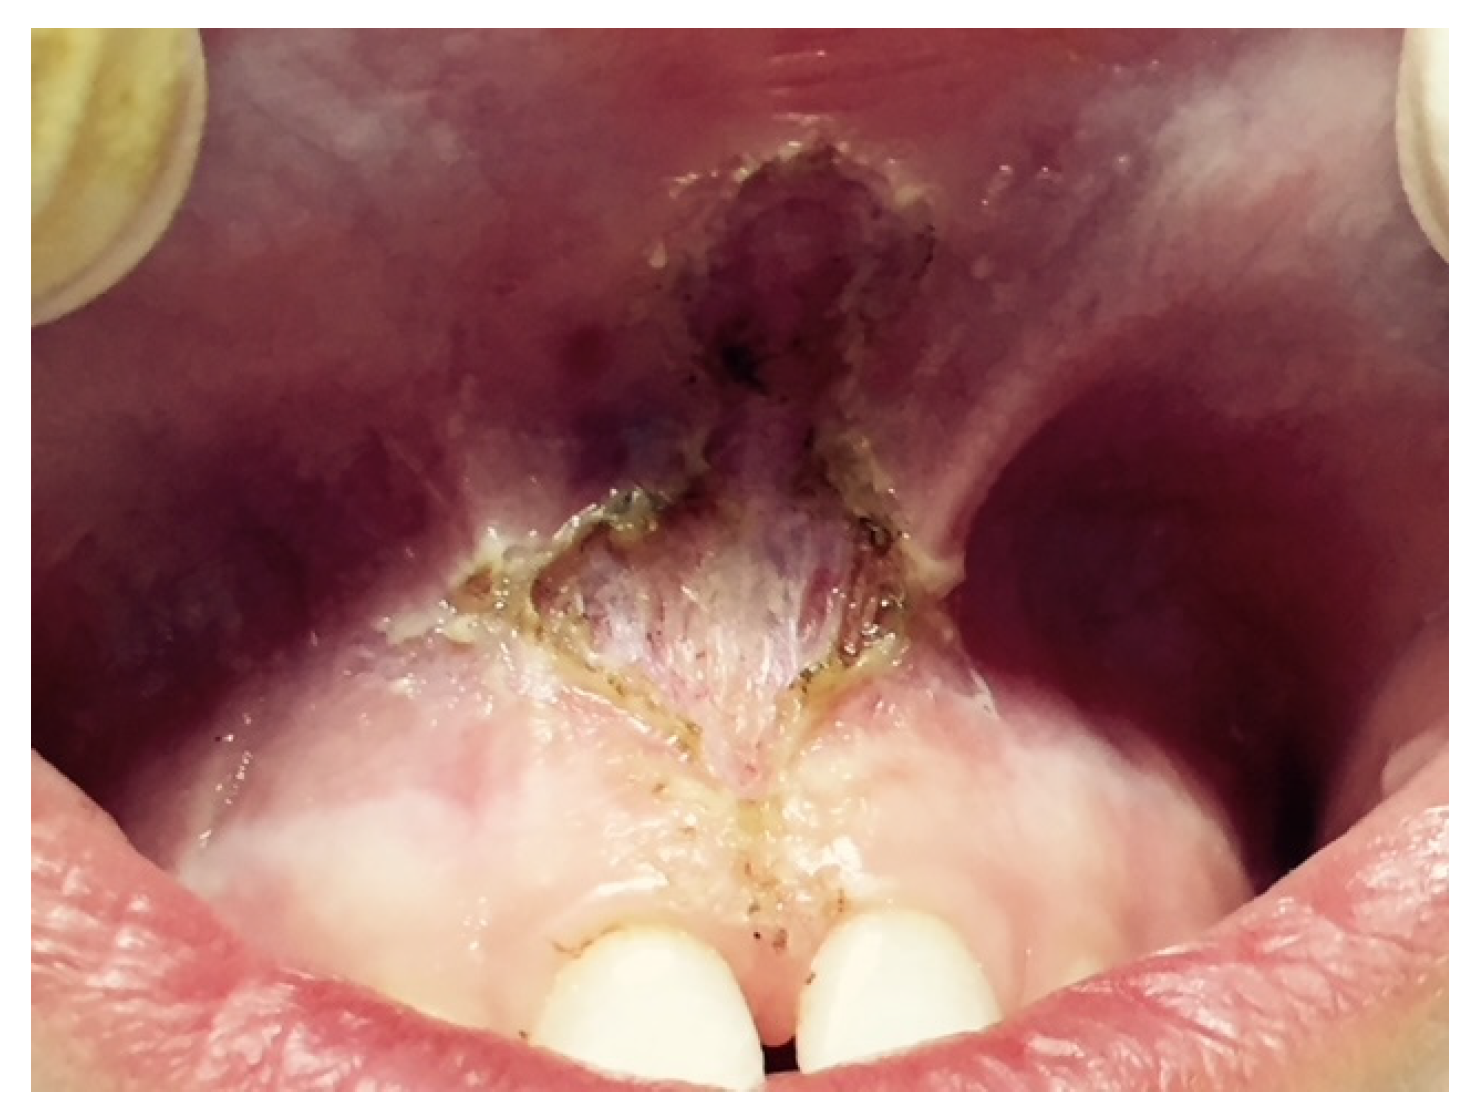

A characteristic of an abnormal frenulum, known as “pull syndrome,” is the ischemization of the palatine papilla and mesial gingival borders of the upper central incisors after traction of the top lip (Figure 1).

Figure 1.

Example of the hypertonic ULF.